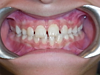

Cas 3

Enfant de 7 ans, occlusion inversée des incisives corrigée par des plaques à pistes de Planas.